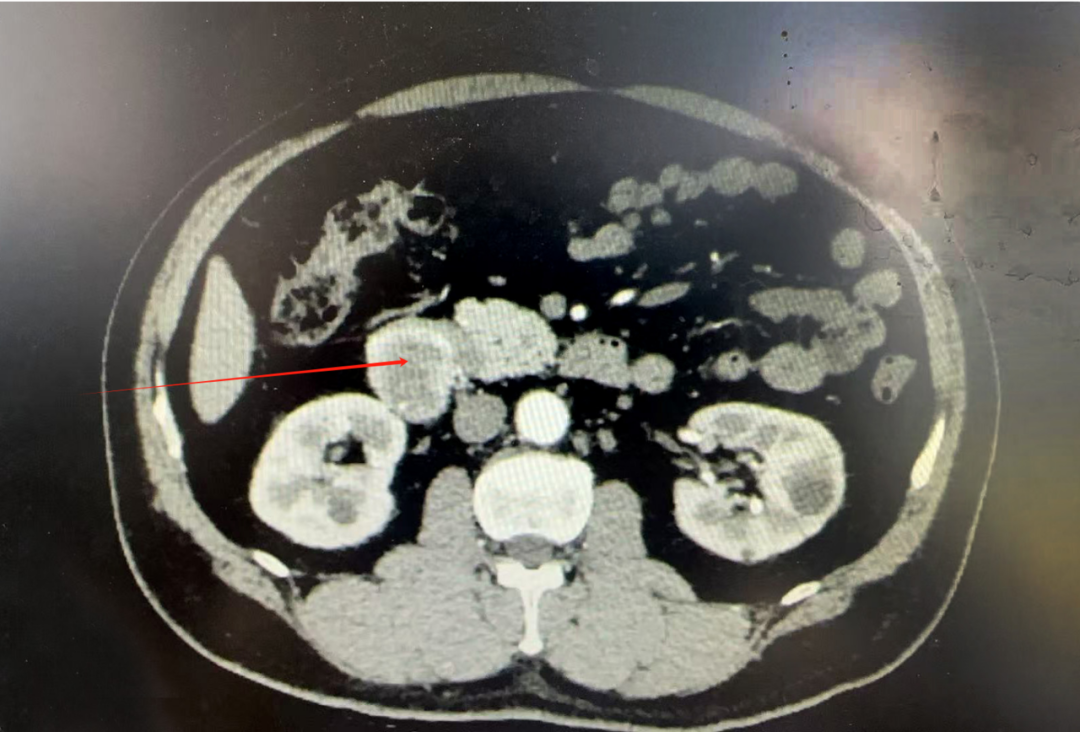

患者李先生,49岁,因“眼黄、尿黄及皮肤黄染半月”逐来我院就诊。腹部CT检查显示:十二指肠降部存在约4cm大小的占位性病变。经综合评估,临床诊断为“十二指肠肿瘤、梗阻性黄疸”。

【术 前 影 像 显 示 】

办理住院后,桂武斌副院长带领外科医疗团队迅速为患者完善各项术前检查,同步开展保肝退黄及对症支持治疗。桂院长牵头组织多次多学科病例讨论,与患者及其家属进行了充分的病情沟通和手术方案讲解。在麻醉科的全力配合下,于2025年6月10日为患者实施气管插管全身麻醉下行“根治性胰十二指肠切除术”。